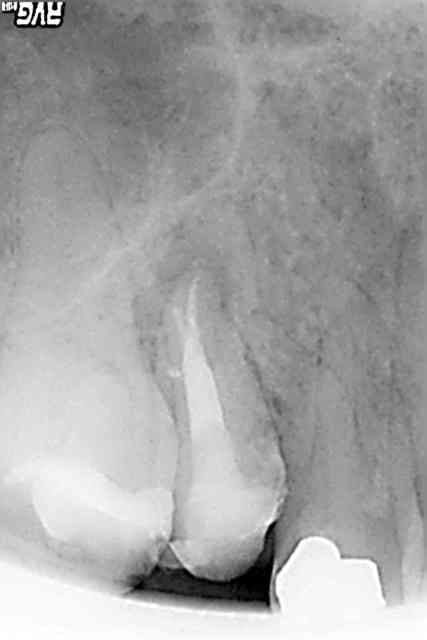

alors j'ai un patient reçu en consultation mi février pour douleur sur une 37 nécrosée.pas de douleur suite au traitement endo et jusqu'a ce jour.alors voila ma question au bout de combien de temp estimer vous que le processus de guerison est en route?et sur quels critères?donc en gros et ce qu'a la vue de la radio post op prise auourdhui je suis en mesure de proposer l'inlay core et la couronne a mon patient ou bien faut il encore attendre???

Merdique ou pas y'a un signe de guerison a la radio, cf l'apex de la racine distale sur lequel l'os commence a revenir

Pour revenir à ton mouton, je trouve ton endo fort correcte, avec cependant un manque d'alésage compte-tenu qu'il s'agit d'une dent initialement infectée.

Mais vue la non-évolution de la lésion et la faisabilité de l'amélioration, je serais toi, je referais un alésage un peu + poussé, à la même longueur (si c'est celle donnée par ton localisateur d'apex, c'est la bonne :o) et SURTOUT beaucoup de javel, longtemps... au moins 15mn (les recommandations sont de l'ordre de 40mn d'après un article de l'ID mais bon...).

Donc, tu désobtures, tu rebouches avec ce que tu veux (on s'en fout! ce que tu fais est déjà très correct)et tu fixes un RV pour l'empreinte de l'IC+CCM dans 15 jours durant lesquels le patient te recontacte si douleurs, sinon, tu peux construire dessus.